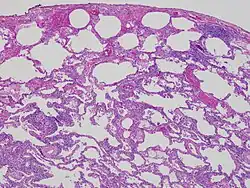

High magnification photomicrograph of a lung biopsy taken showing chronic hypersensitivity pneumonitis (H&E), showing mild thickening of the walls of the small air sacs by invasion of white blood cells. A multinucleated giant cell, seen within the walls of the air sacs to the right of the picture halfway down, is an important clue to the correct diagnosis.

Low magnification view of the histology of chronic hypersensitivity pneumonitis. The interstitium is expanded by a chronic inflammatory infiltrate. Two multinucleated giant cells can be seen within the interstitium at left, and a plug of organizing pneumonia at bottom left.

Lung biopsies can be diagnostic in cases of chronic hypersensitivity pneumonitis, or may help to suggest the diagnosis and trigger or intensify the search for an allergen. The main feature of chronic hypersensitivity pneumonitis on lung biopsies is expansion of the interstitium by lymphocytes accompanied by an occasional multinucleated giant cell or loose granuloma.[7][22]

When fibrosis develops in chronic hypersensitivity pneumonitis, the differential diagnosis in lung biopsies includes the idiopathic interstitial pneumonias.[23] This group of diseases includes usual interstitial pneumonia, non-specific interstitial pneumonia and cryptogenic organizing pneumonia, among others.[7][22]

The prognosis of some idiopathic interstitial pneumonias, e.g. idiopathic usual interstitial pneumonia (i.e. idiopathic pulmonary fibrosis), are very poor and the treatments of little help. This contrasts the prognosis (and treatment) for hypersensitivity pneumonitis, which is generally fairly good if the allergen is identified and exposures to it significantly reduced or eliminated. Thus, a lung biopsy, in some cases, may make a decisive difference.